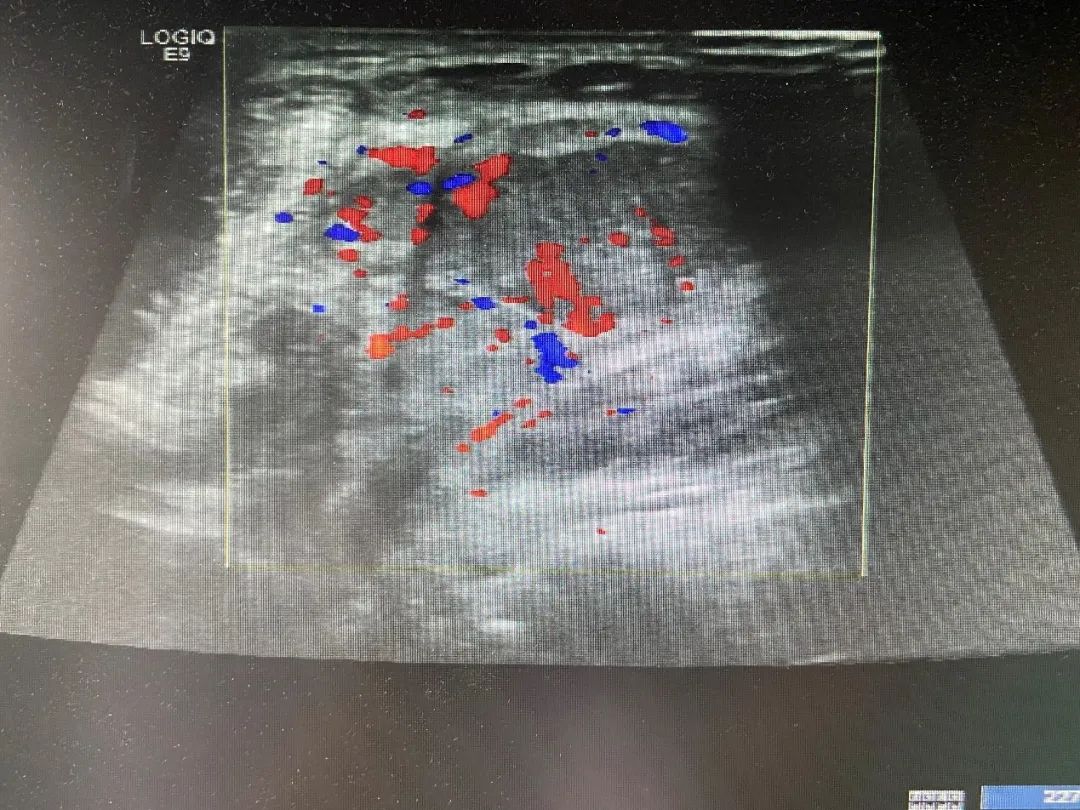

图 3 颈部肿大淋巴结血流

CDFI 可见较丰富血流信号